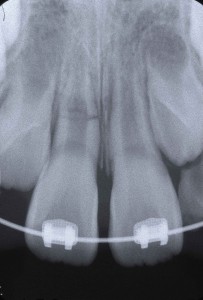

右上中切歯(右の真ん中の歯)は歯根破折、左上中切歯は歯牙脱臼を起こしていました。脱臼については、そこそこ固定できればどのような方法でもくっついてくれますが、歯根破折の場合は、処置によって大きく結果が異なります。

ポイントは「元あった位置にいかにピッタリ戻し、その位置で強固に固定できるか」ということです。この症例では、横の乳歯が一方はない、もう一方がぐらぐらしているということで固定源としては使えませんので、一つ飛ばして真ん中から3番目の乳歯にそれを求めなければなりません。

さらに固定した位置がずれないように、また、割れている部位に介在している一日経って弾力が出てしまった血餅をつぶしながらの固定ですから、大きな硬いワイヤーを曲げて使用しなければ目的を達することができない難しさもあります(血餅の排除に限度があったため、僅かな隙間は存在します)。

さらに固定した位置がずれないように、また、割れている部位に介在している一日経って弾力が出てしまった血餅をつぶしながらの固定ですから、大きな硬いワイヤーを曲げて使用しなければ目的を達することができない難しさもあります(血餅の排除に限度があったため、僅かな隙間は存在します)。